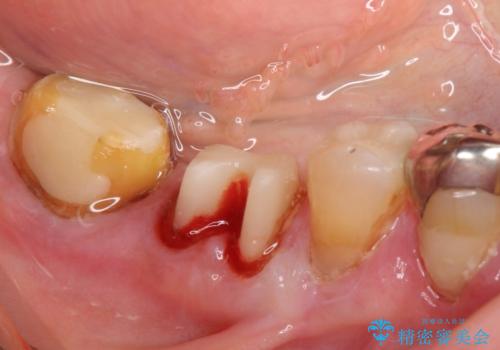

- 歯ぐきからの出血と腫れを主訴に来院された患者様です。

プラークコントロールが非常に悪く、全顎的な歯周病に罹患していました。

「抜歯したくない、インプラントは嫌」という患者様のご希望とご年齢を考慮し、可及的な骨外科処置や根分割術によりできるだけ今ある歯を残す治療方針をたてました。

ご希望により、積極的な再根管治療は行いませんでした。